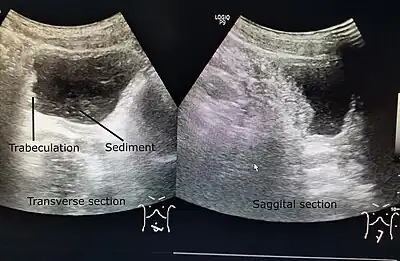

| A paraplegic patient with neurogenic bladder on regular ultrasound follow-up showing thickened bladder wall with trabeculations and sediments within the bladder. | |

Ultrasound imaging can give information on the shape of the bladder, post-void residual volume, and evidence of kidney damage such as kidney size, thickness or ureteral dilation.[9] Trabeculated bladder on ultrasound indicates high risk of developing urinary tract abnormalities such as hydronephrosis and stones.[10] A voiding cystourethrography study uses contrast dye to obtain images of the bladder both when it is full and after urination which can show changes in bladder shape consistent with neurogenic bladder.[9]